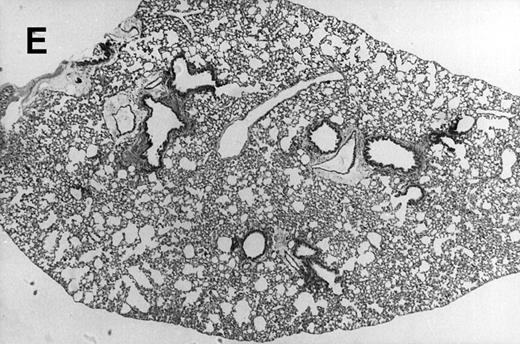

Allogeneic transplanted mice (B10.BR → CBA) with GVHD and, as controls, allogeneic transplanted mice without GVHD and syngeneic transplanted mice (B10.BR → B10.BR) were infected intranasally with HSV-1 at 12 weeks after transplantation. As an additional control, age-matched normal CBA mice were infected as well. Histological examination of lungs was performed in mock-infected mice and in mice at day 7 after infection. Allogeneic transplant recipients with GVHD showed increased pathology (Fig 1). Scores reflecting the periluminal histopathologic changes were significantly higher (P = .05; Student's t-test) in allogeneic transplant recipients with GVHD, when compared with control mice (Fig 2). The periluminal histopathologic scores were also higher in allogeneic transplant recipients with GVHD, when compared with normal CBA mice, at days 4, 10, and 14 after infection (data not shown). No significant differences were observed in the scores reflecting the parenchymal histopathologic changes (data not shown). Because the results in syngeneic transplanted mice were very similar to those in allogeneic transplanted mice without GVHD, the latter, which are the most appropriate control for procedural effects and for the effect of GVHD, and normal CBA mice, were used as controls in further experiments.

Allogeneic transplant recipients with GVHD showed increased pathology. Photomicrographs of lung sections stained with hematoxylin and eosin show evidence of increased pathology in infected allogeneic GVHD mice. (A) Normal CBA, mock-infected, original magnification × 25; (B) normal CBA, mock-infected, original magnification × 100; (C) normal CBA, infected, original magnification × 40; (D) normal CBA, infected, original magnification × 100; (E) allogeneic GVHD, mock-infected, original magnification × 10; (F) allogeneic GVHD, mock-infected, original magnification × 75; (G) allogeneic GVHD, infected, original magnification × 10; (H) allogeneic GVHD, infected, original magnification × 100.